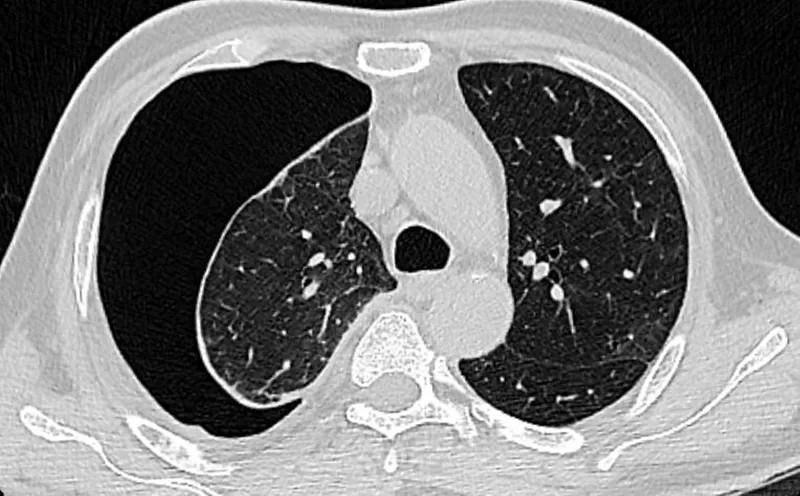

医生检查后发现,小玲的右肺像气球一样被扎破了,胸腔内充气形成右侧气胸,右肺已被压缩40%,必须立即进行手术将漏气“放出”。